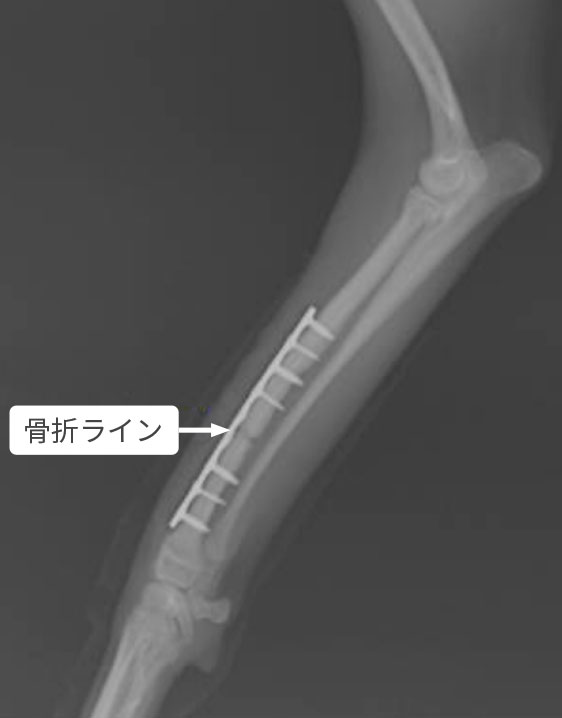

KYON社のALPSプレートとスクリューはチタン製で骨に親和性が高く、プレートの形状がポイントコンタクト(点で支える)のため骨膜の血行を妨げることなく骨の再生を促し、骨折の治癒を促進します。

ALPSシステム

構造

通常のプレート

当院で採用しているプレート